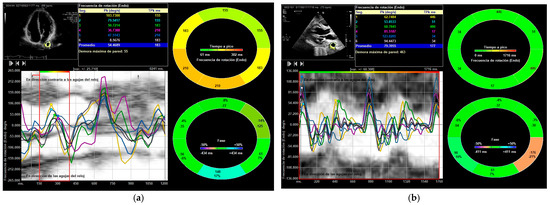

| DTA rotational velocity (°/s) | N = 178; 55.44 ± 16.15 | N = 178; 88.98 ± 10.31 |

| DTA radial velocity (cm/s) | N = 144; 1.02 ± 0.36 | N = 144; 1.56 ± 0.42 |

| DTA circumferential strain (%) | N = 149; −8.52 ± 0.31 | N = 149; −12.55 ± 1.13 |

| DTA strain-rate circumferential aorta (1/s) | N = 156; −1.55 ± 0.72 | N = 138; −2.28 ± 0.56 |

| DTA rotational displacement (°) | N = 168; 6.22 ± 0.36 | N = 168; 14.91 ± 0.85 |

| DTA aorta radial displacement (mm) | N = 178; 0.89 ± 0.31 | N = 164; 1.19 ± 0.65 |